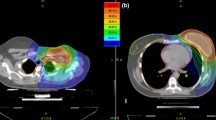

While the corresponding EAR50–70 can be obtained by simply scaling the EAR0 coefficients (see “Risk modelling” section), it is interesting to evaluate the difference in EAR obtained for the same patient, assuming the irradiation at an age of 30 or 50 years, while keeping the attained age of 70 years constant. Delta-EAR (ΔEAR = EAR30–70 − EAR50–70) was thus computed and the data are summarized in Fig. 3.

EAR difference as a function of the age of exposure (EAR30–70–EAR50–70) for the single patients included in the analysis. The EAR difference is shown for the contralateral breast for Group 1 patients treated with tangential 3D-CRT vs PT (top panel) and for Group 2 patients treated with VMAT versus PT in the case of FB (middle panel) and DIBH (bottom panel)

The ΔEAR associated to the contralateral breast is remarkably higher for Group 2 patients treated with VMAT, with absolute values depending on the dose–response model and minor difference between FB and DIBH. This is a consequence of the marked EAR0 reduction for older patients (9.2 vs 3.7 cases per 10,000 persons per year per Gy). In details, data show a reduction in contralateral breast SCR for VMAT by about 60% for patients exposed at 50 rather than at 30 years. A smaller effect is observed for tangential 3D-CRT in Group 1, which is explained by the lower OAR doses due to the different target, while no substantial changes are always associated to PT, independently on the specific target configuration, because of the very low dose released to the contralateral breast and the extremely low EAR associated. Due to minor difference in EAR0 (7.5 vs 7.8 cases per 10,000 persons per year per Gy), a minor ΔEAR is attributed to the lungs (not shown).